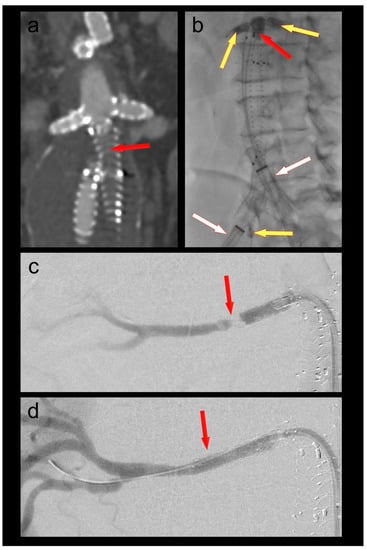

A 70-year-old male patient who had undergone a 4-fenestration endovascular aneurysm repair (EVAR) 6 months prior was admitted with new-onset short-distance claudication of his right leg. CT angiography revealed a complete occlusion of the right EVAR limb and a non-occlusive thrombus in the left limb. The renal fenestrations/origins of the renal bridging stentgrafts were only a few millimeters above the graft bifurcation (Figure 1). Both renal bridging stentgrafts and the right hypogastric artery were protected using 3F OTW Fogarty® catheters over 0.018″ guide wires. The left hypogastric artery was protected by advancing the sheath into the distal EVAR limb. A thrombectomy of both limbs was performed using a 6F Fogarty® catheter (Figure 1). An iatrogenic dissection of the right renal artery at the distal end of the bridging stent graft was treated by implantation of a 5 × 25 mm Gore® Viabahn self-expandable stent graft. Postoperative CT-scan showed complete thrombectomy of both limbs and ruled out any embolization of the renal and hypogastric arteries (Figure 1).

Figure 1. (a) Thrombotic occlusion of the right EVAR limb (ballerina situation) (red arrow); (b) thrombectomy of the graft limb (red arrow) under balloon protection of both renal bridging stentgrafts and the right hypogastric artery (yellow arrows). The large-bore sheaths are occlusive in the left graft limb and in the right external iliac artery (white arrows); (c) Iatrogenic dissection of the right renal artery (red arrow); (d) Right renal artery after implantation of a self-expanding stent graft (red arrow).